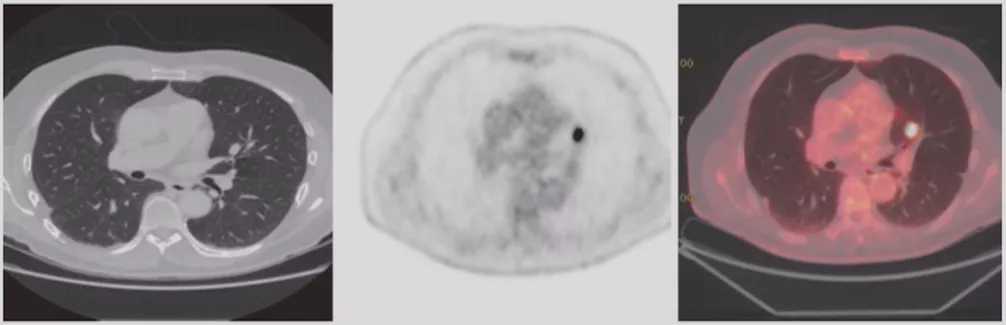

PET-CT

PET-CT对肺结节有一定作用,不同大小、不同类型的肺结节,有不同的诊断价值。但对于纯GGO,PET-CT的诊断价值有限;而对于部分实性GGO,PET-CT有一定价值。指南仅推荐>8mm实性结节或实性成分>8mm且具有高危因素可行PET检查。